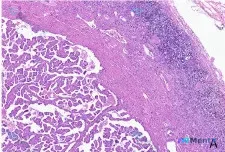

今天整理了一份肾脏肿瘤的病理读片资料,觉得挺有代表性,尤其是容易踩的思维陷阱,分享一下思路。 先看基本资料 - 病理背景:标本为肾脏肿瘤组织,HE染色,低倍镜(x40)视野 - 原始描述:肿瘤边界清晰,有纤维假包膜,包膜边缘大量淋巴细胞浸润 影像/镜下核心表现 从图像和补充描述来看,有几个明确的特点...